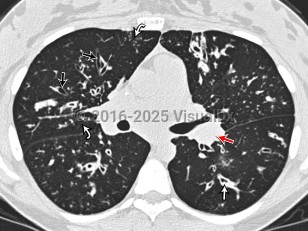

Cystic fibrosis is a congenital metabolic disorder caused by a mutation in a protein that regulates chloride ion transport. This leads to viscous secretions and eventual dysfunction of exocrine glands, most notably affecting the lungs and pancreas. Symptoms usually appear in childhood and include recurrent pulmonary infections with gradual loss of pulmonary function and pancreatic insufficiency leading to poor weight gain. Liver involvement can range from steatosis to advanced cirrhosis with portal hypertension.

Only about 4% of cystic fibrosis patients are diagnosed as adults. Adult patients may also develop pancreatic endocrine insufficiency and cystic fibrosis-related diabetes, which involves both insulin deficiency and resistance. Most adult cystic fibrosis patients will ultimately die of respiratory failure.